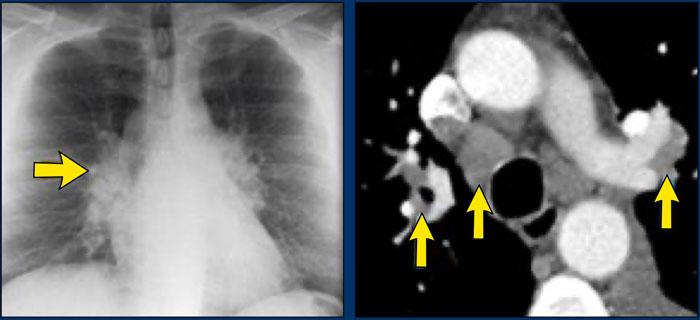

Bên trái là bệnh nhân nữ 47 tuổi với triệu chứng ho khan, khó thở nhẹ và xét nghiệm máu bình thường.

Bệnh nhân được chụp X-quang ngực và điều trị kháng sinh.

Phim kiểm tra được chụp lại do bệnh nhân không cải thiện.

Phim X-quang ngực đầu tiên cho thấy đông đặc hai bên ở thùy dưới (mũi tên), ban đầu được diễn giải là nhiễm trùng.

Sau hai tuần điều trị kháng sinh, không có cải thiện.

Chẩn đoán phân biệt lúc này bao gồm u ác tính (ung thư phế quản phế nang hoặc u lympho), viêm phổi tăng bạch cầu ái toan, viêm phổi tổ chức hóa, bệnh Wegener hoặc một thể không điển hình của sarcoidosis.

Tiếp tục với hình ảnh HRCT.

Có nhiều vùng đông đặc.

Các dấu hiệu kèm theo bao gồm hạch to rốn phổi và trung thất.

Chẩn đoán phân biệt trên hình ảnh CT về cơ bản giống như trên X-quang ngực.

Kết quả mô bệnh học xác nhận sarcoidosis phế nang.

Chỉ có một gợi ý duy nhất cho chẩn đoán, đó là sự hiện diện của các nốt nhỏ có thể nhận thấy ở hình 3, nhưng rất khó quan sát.

Trường hợp này minh họa rõ ràng rằng sarcoidosis thực sự là “kẻ bắt chước vĩ đại”.

Do đó, sarcoidosis cần được đưa vào danh sách chẩn đoán phân biệt của chúng ta!